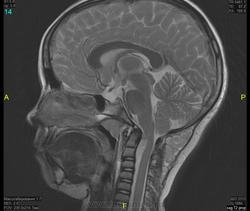

Уважаемые коллеги! Прошу консультативной помощи. Про пациента известно: девочка (7 лет), в анамнезе 2,5 года назад травма головы. Не диагностировалась. Периодически жалобы на болезненность при пальпации затылочной области(((((

Напоминает сосудистую структуру.Может, какая-нибудь лимфангиома?Видела на передней поверхности шеи, на задней - нет.

как будто связь с ликвором имеется.  Дополнил бы венографией, и FatSat"ом ну и контрастом, конечно.

Сегодня в ходе разговора с мамой девочки, выяснилось, что и у мамы есть подобное "образование". С ее слов, несколько лет назад ей делали пункцию для исключения онкологии. Результат пункции: содержится нервная ткань и лимфоциты ( опять же никаких документов я не видела). То есть можно говорить о наследственном характере.

Нейрофиброма вполне может быть. Плексиформная. Проверить на нейрофиброматоз. Я видел такой же структуры и локализации. Пятен на коже нет? Вообще на теле? И нет ли чего похожего в позадиглоточном пространстве?

есть похожее образование в позадиглоточном пространстве)

многоузловое образование  исходящее из задней части предпозвоночного пространства с переходом на подкожную жировую клетчатку головы!шваннома ,нейрофиброма и их злокачественные аналоги